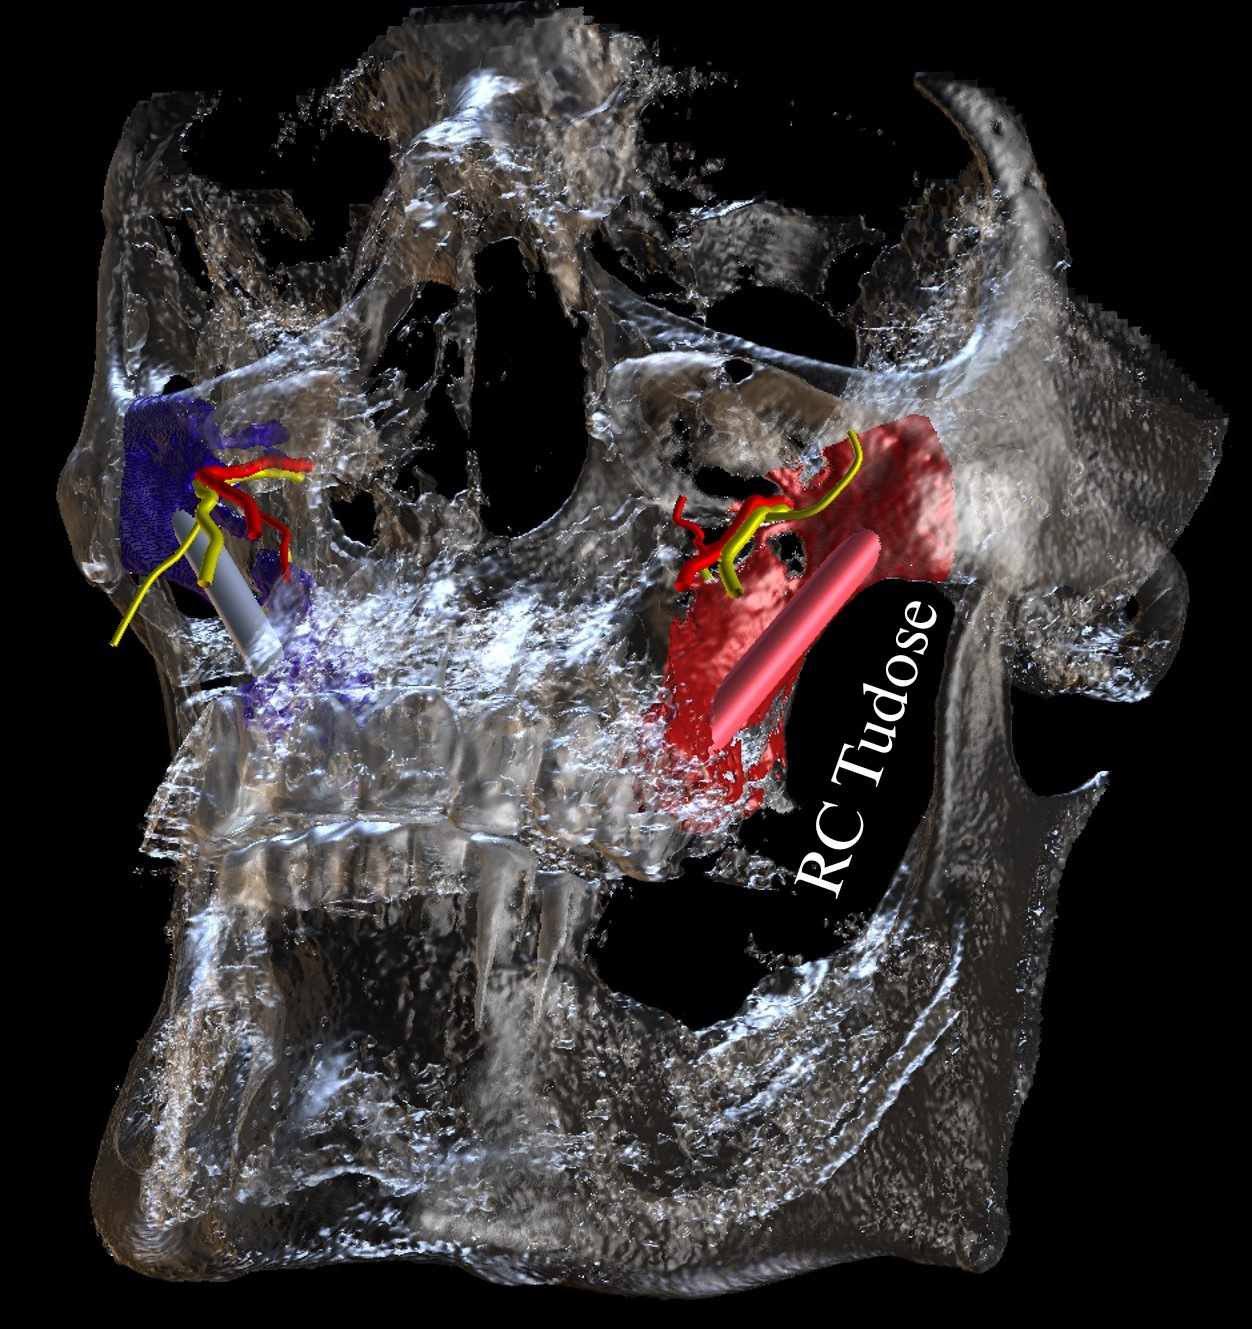

Oral Presentation - CBCT assessment of the greater palatine canal

Oral Presentation - The Zygomatic Implant: An anatomical view of the potential risks